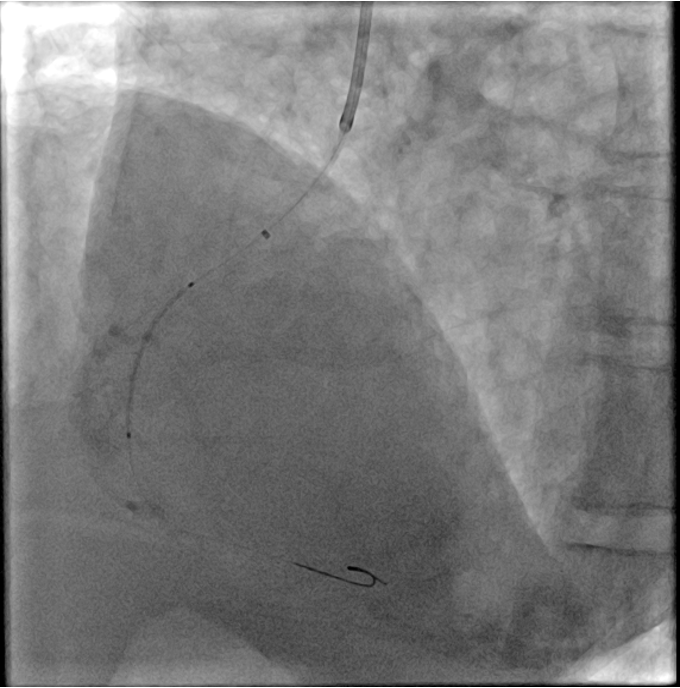

Coronary angiography of the RCA was initially attempted using a Tiger 3.5 5 F and a JR 4.0 5 F catheter but proved unsuccessful. A JL 3.5 5 F catheter was subsequently employed to selectively engage the left coronary sinus; however, after 30 minutes, selective cannulation could not be achieved. Guided by CTA findings, a JR 4.0 6 F guiding catheter was advanced, and with the gantry positioned at RAO 22 ¡Æ, successful selective cannulation of the RCA was achieved with ease.

Percutaneous intervention of the right coronary artery was performed using a JR 4.0 6 F guiding catheter, with a Sion Blue wire advanced across the lesion with ease. However, due to severe calcification and an anomalous ostium with a sharp 90 ¡Æ angulation immediately after the take-off, additional support with a ¡°mother-and-child¡± guiding catheter was required. Lesion preparation was carried out using a 2.0 ¡¿ 15 mm compliant balloon, followed by sequential deployment of two drug-eluting stents: 2.5 ¡¿ 26 mm and 3.0 ¡¿ 24 mm. post-dilation was performed with non-compliant balloons sized 3.0 ¡¿ 12 mm and 3.5 ¡¿ 15 mm. Final angiography demonstrated optimal results with TIMI 3 flow.